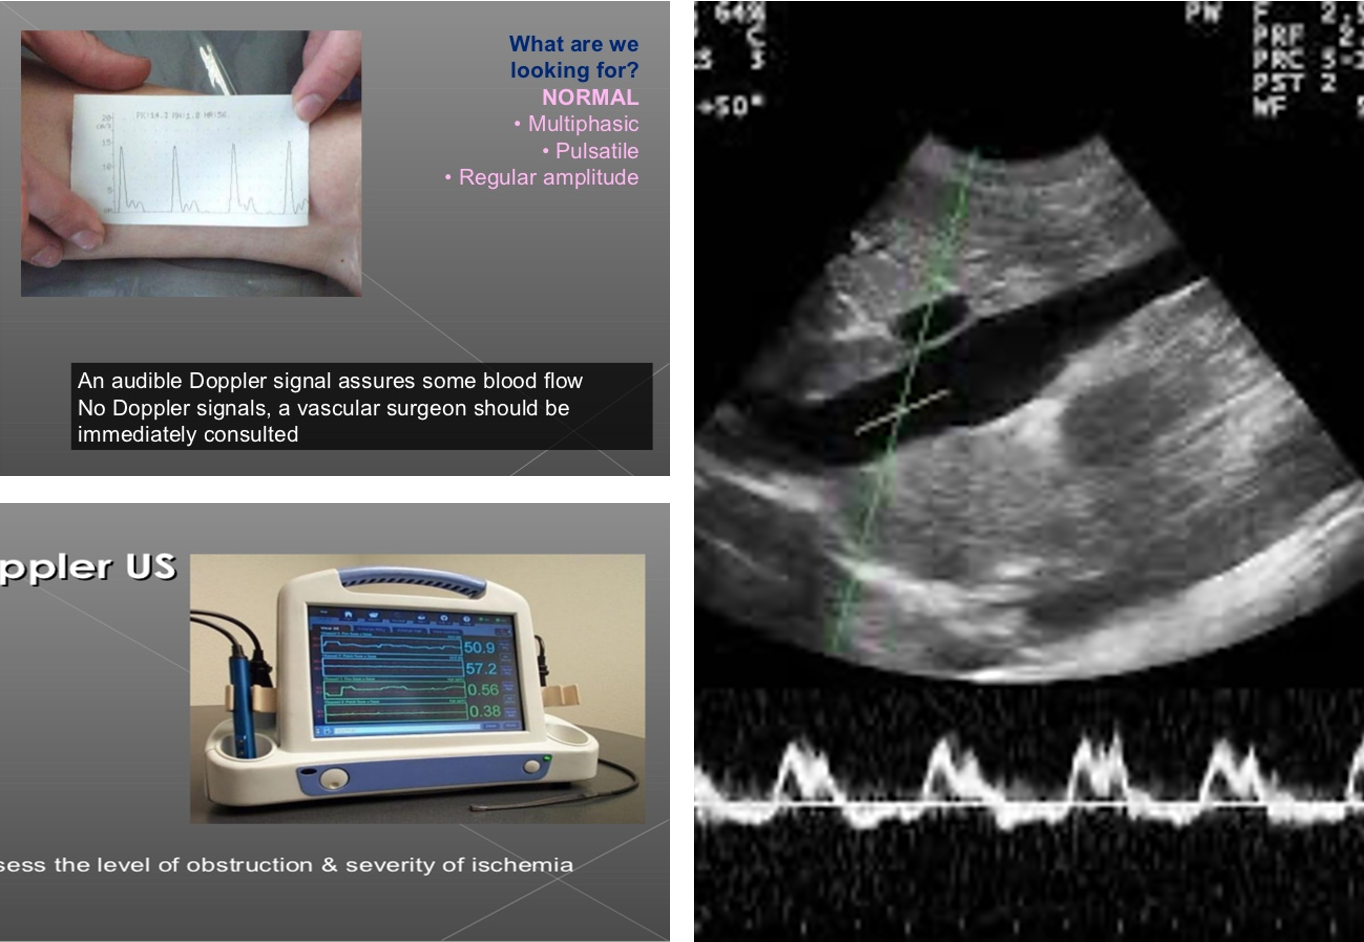

Doppler Vs Dopplux

Multiphasic normal one -

duplex waves + picture